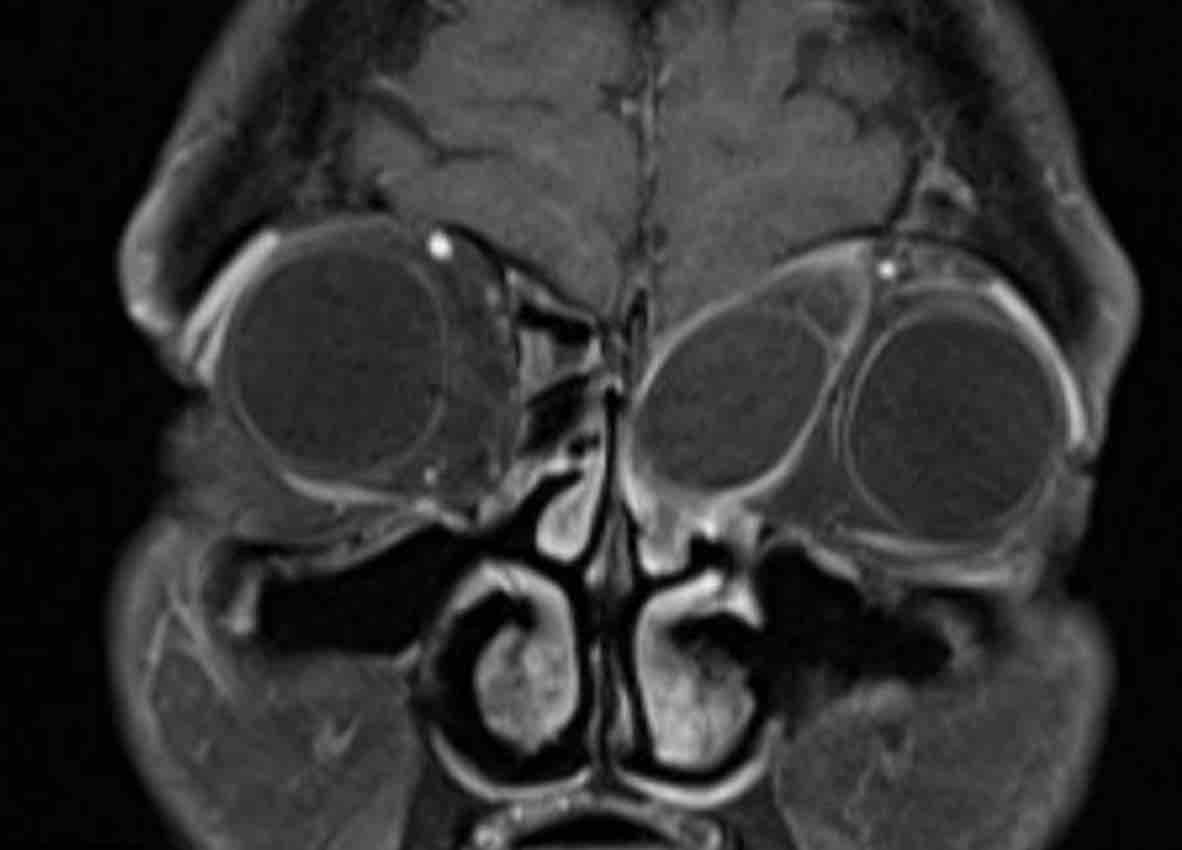

Các hình ảnh này của một bệnh nhân nam 16 tuổi với biểu hiện lồi mắt và chảy máu mũi.

Trên các hình ảnh này, có một tổn thương phá hủy xương với xâm lấn vào hốc mắt.

MRI cho thấy một khối u phá hủy một bên với hạn chế khuếch tán rõ rệt (giảm tín hiệu trên bản đồ ADC).

Như vậy, chúng ta có ba dấu hiệu cảnh báo.

Hạn chế khuếch tán là một lập luận khác chống lại chẩn đoán u xơ mạch máu vị thành niên, vì một tổn thương mạch máu sẽ không gây ra hạn chế khuếch tán.

Có xâm lấn vào hốc mắt và cả vào phần mềm phía trước của má (mũi tên).

Sinh thiết được thực hiện và cho kết quả là u cơ vân (rhabdomyosarcoma), được điều trị bằng hóa trị liệu.